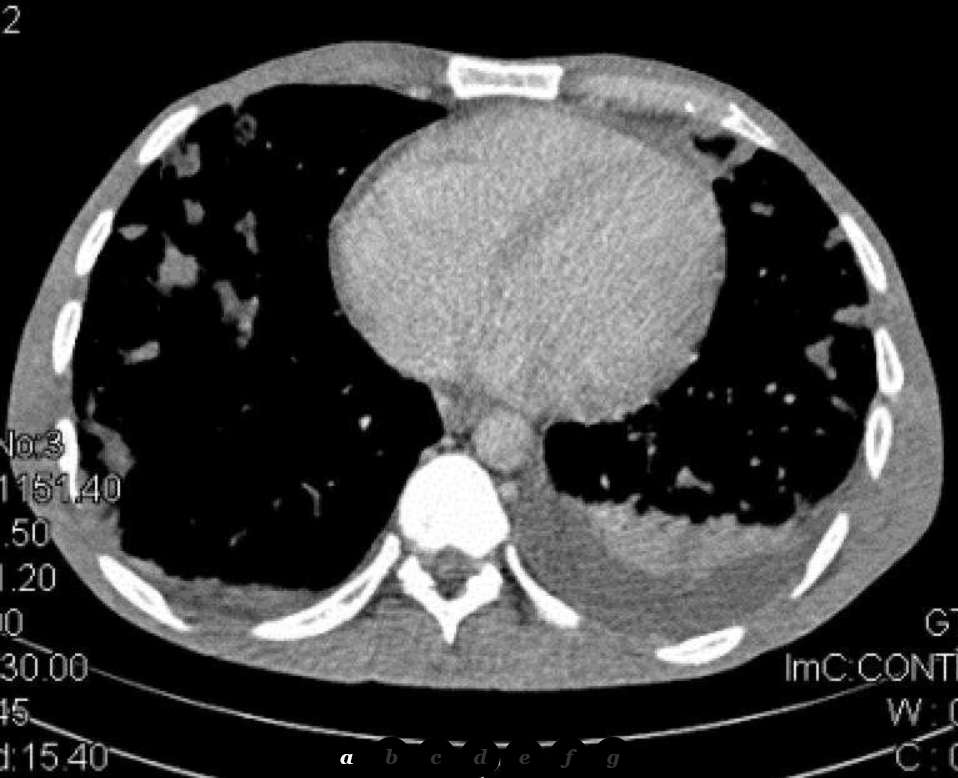

The patient was then referred for chest Computed Tomography which confirmed the presence of multiple and widespread irregular pulmonary nodules in both lungs. Some of these nodules were cavitated. The “feeding vessel sign” was also noted in some of the nodules which were directly connected with a vessel. There was also a small left pleural effusion (Fig. 2).

Multi-Planar Reconstruction further helped in interpreting the radiographic findings and in evaluating the extent of the disease.

The typical CT image of PSE comprises multiple round densities with or without cavitation which are located diffusely in both lungs but with a lower lobe predilection. There may also be a pericardial or pleural effusion and air bronchogram within pulmonary nodules. Septic foci are less distinctly demarcated than metastases and may have a wedge-like shape with their base on the pleura [1, 2].

With the use of an IV contrast medium, the densities are enhanced in their periphery or in a rimlike pattern. When the septic infiltrates subside, follow-up CT examinations may reveal subpleural linear strands [3]. Empyema is a common complication of PSE which can be discovered by CT [6]. The “feeding vessel sign” characterizes PSE and describes the connection of the density with a distinct pulmonary vessel leading into its centre and proves the haematogenous origin of the lesion. It is easily identified on CT when the feeding vessel lies in the same plane with the nodule [2, 3]. Albeit its high prevalence, the feeding vessel sign may not be true, as recent studies showed that MDCT mutliplanar images prove some feeding vessels to course around the nodules or to represent pulmonary veins. The same sign may also be caused by metastases [7].